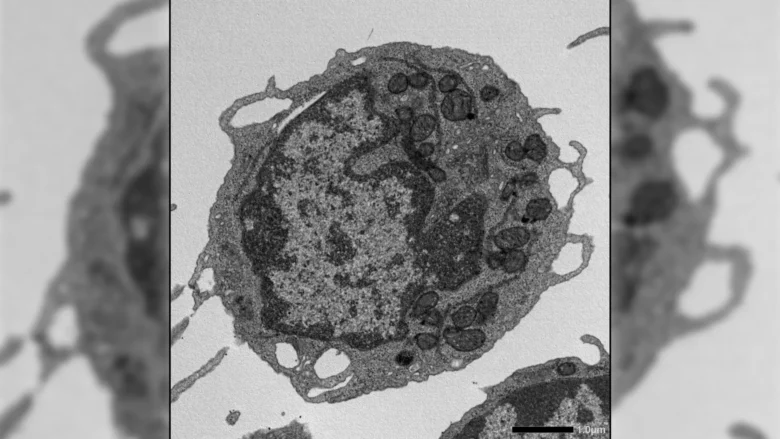

Mitochondrial Damage Without Cell Death

The results revealed a previously unknown role for MLKL in stem cell aging. Although MLKL is usually linked to cell death, its activation in HSCs did not increase cell death or reduce cell numbers. Instead, it acted in a different way.

When activated under stress, MLKL briefly moved to the mitochondria, the structures that generate energy within cells. There, it caused damage by lowering membrane potential, altering mitochondrial structure, and reducing energy production. These effects led to key features of aging in HSCs, including reduced ability to renew themselves, decreased production of lymphoid cells, and a shift toward myeloid cell output.